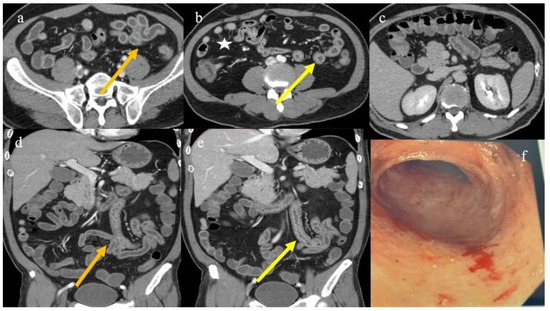

| 1 | P | P | Multisegmental and plurifocal parietal thickness with homogeneous mucosal enhancement on distal ileus | Multisegmental thickness with homogeneous mucosal enhancement | Mild diffuse comb sign and poor reactive mesenteric lymph node | Splenic infarct |

| 2 | P | P | Diffuse parietal thickness with stratified enhancement | Multisegmental thickness with homogeneous mucosal enhancement | Diffuse comb sign and poor reactive mesenteric lymph node | Mild gallbladder thickness and mild biliary tract dilatation |